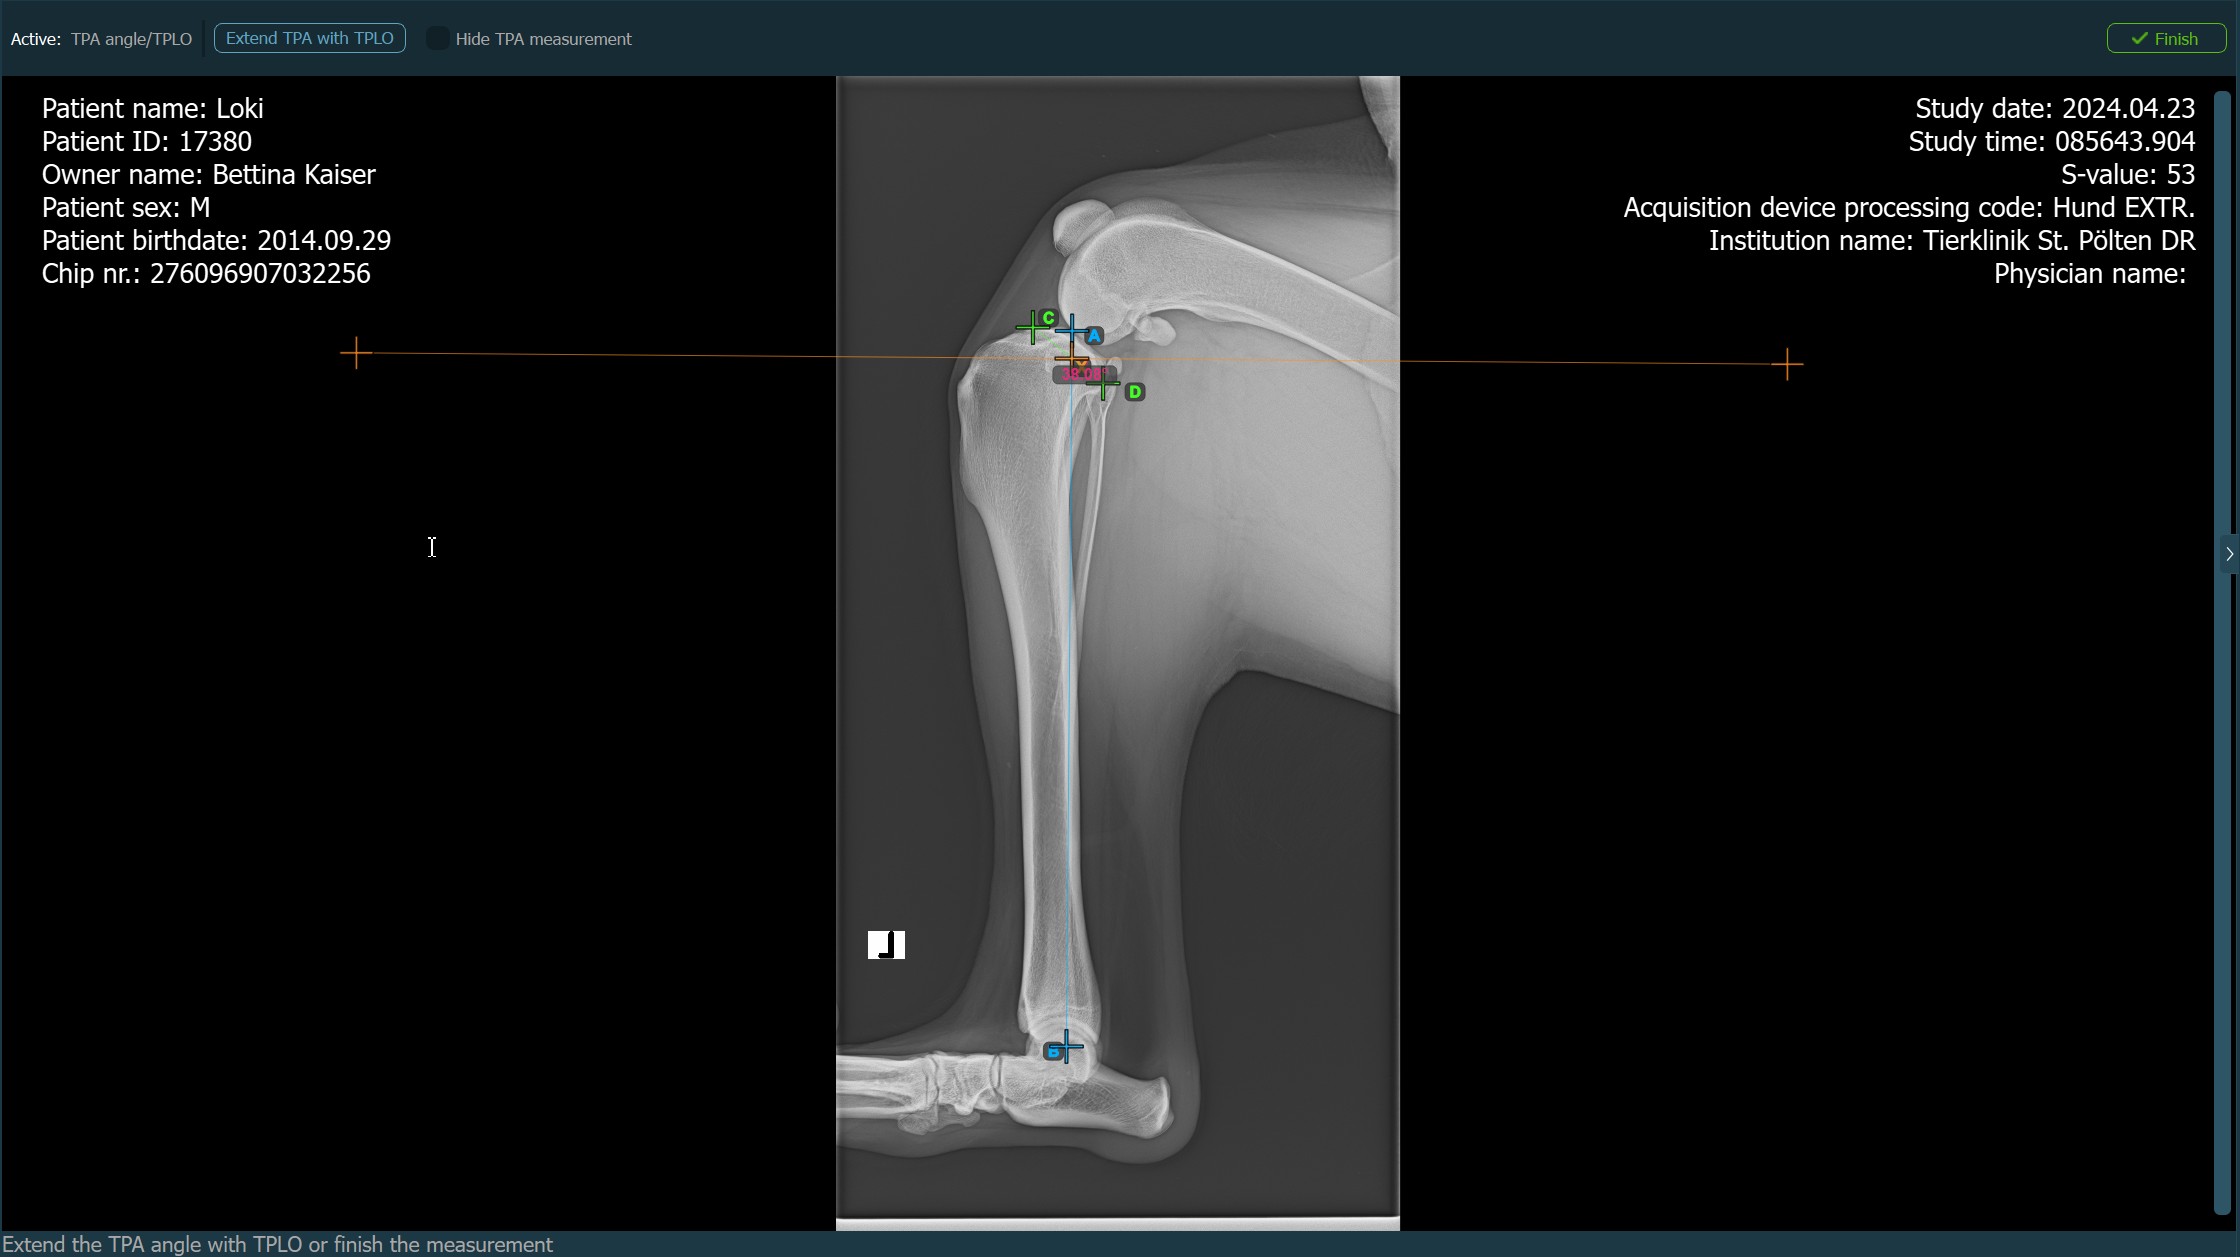

TPA-Winkel/TPLO¶

Der TPA-Winkel (Tibial Plateau Angle) ist eine der wichtigsten orthopädischen Messungen in der Veterinärmedizin und misst die Neigung des Tibiaplateaus relativ zur Längsachse der Tibia. Wählen Sie die Messung TPA-Winkel aus dem Erweiterten Messmenü und weisen Sie ihr die linke Maustaste zu.

Die TPA-Winkel-Messung ist ein entscheidender Bestandteil der Planung von Korrekturoperationen wie TPLO (Tibial Plateau Leveling Osteotomy). Erweitern Sie die TPA-Winkel-Messung mit TPLO in den Einstellungen des einfachen Viewers.

Wenn die TPLO-Erweiterung zur TPA-Winkel-Messung aktiviert ist, wählen Sie eine der verfügbaren Optionen aus der Symbolleiste des erweiterten Messmodus, um die Messung fortzusetzen/abzuschließen. Andernfalls wird die TPA-Winkel-Messung automatisch abgeschlossen.

Drücken Sie

Fertigstellen, um die TPA-Winkel-Messung ohne TPLO-Erweiterung zu bestätigen und abzuschließen.Aktivieren Sie die TPLO-Erweiterung, indem Sie die Schaltfläche

TPA mit TPLO erweiternverwenden.Blenden Sie die TPA-Winkel-Messung während der TPLO-Erweiterung ein oder aus, indem Sie das Kontrollkästchen

Starten Sie die TPLO-Erweiterung, indem Sie den Tibiakamm markieren. Die Größe der Sägeblattklinge für die TPLO-Erweiterung wird automatisch als Abstand zwischen der Eminentia Intercondylaris und dem Punkt berechnet, der zwei Drittel entlang der Linie zwischen dem hintersten Punkt des Tibiakopfes und dem Tibiakamm liegt.

Das Bild unten zeigt die übliche Platzierung des Punkts am Tibiakamm auf dem Tibiakopf.

Bevor die TPLO-Erweiterung abgeschlossen wird, können Benutzer die Parameter der Messung ändern, die zur Berechnung der Rotationsstrecke für das Verfahren in der Symbolleiste des erweiterten Messmodus erforderlich sind.

Drücken Sie Rotationsstrecke berechnen, um die erforderlichen Berechnungen für das TPLO-Verfahren durchzuführen. Die berechnete Rotationsstrecke wird in der Symbolleiste des erweiterten Messmodus angezeigt.

Die TPA-Winkel-Messung mit TPLO-Erweiterung bleibt aktiv, bis der Benutzer die Schaltfläche Fertigstellen in der rechten Ecke der Symbolleiste des erweiterten Messmodus drückt.